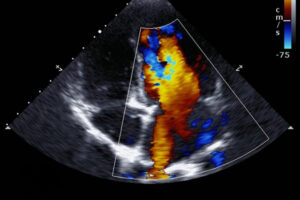

2 D Echo

2D echo is a non-invasive test used to analyze the functioning and assess the sections of your heart. This test gives images of the different